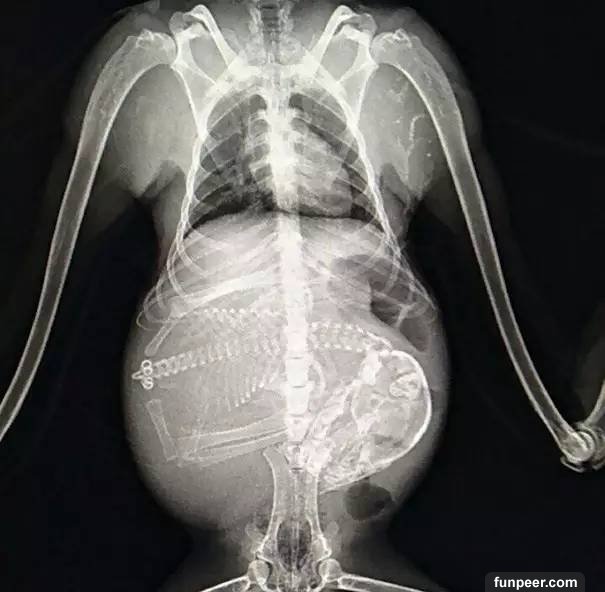

是驚悚還是萌:動物懷孕X光照

之前發過一部分動物懷孕後拍攝的X光照,最近照片又更新了,繼續來感受下: 這是一隻狗媽媽,數一下似乎是懷了七隻小狗